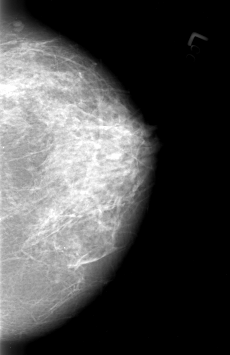

B_3012_1.RIGHT_CC

LEFT_CC LINES 4256 PIXELS_PER_LINE 2752 BITS_PER_PIXEL 12 RESOLUTION 50 NON_OVERLAY